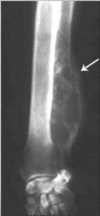

What are Retained endochondral cartilage cores?

A

Disturbed ossification phenomenon seen in

Young large or giant dogs.

Most commonly distal metaphysis of ulna.

Cause unknown for certain. Overnutrition, food additives theorized.

Bilateral symmetrical changes

Shortening of general length, mimics traumatic premature closure of growth plate.

In the image: the flame shaped radiolucent area with sclerotic rim.